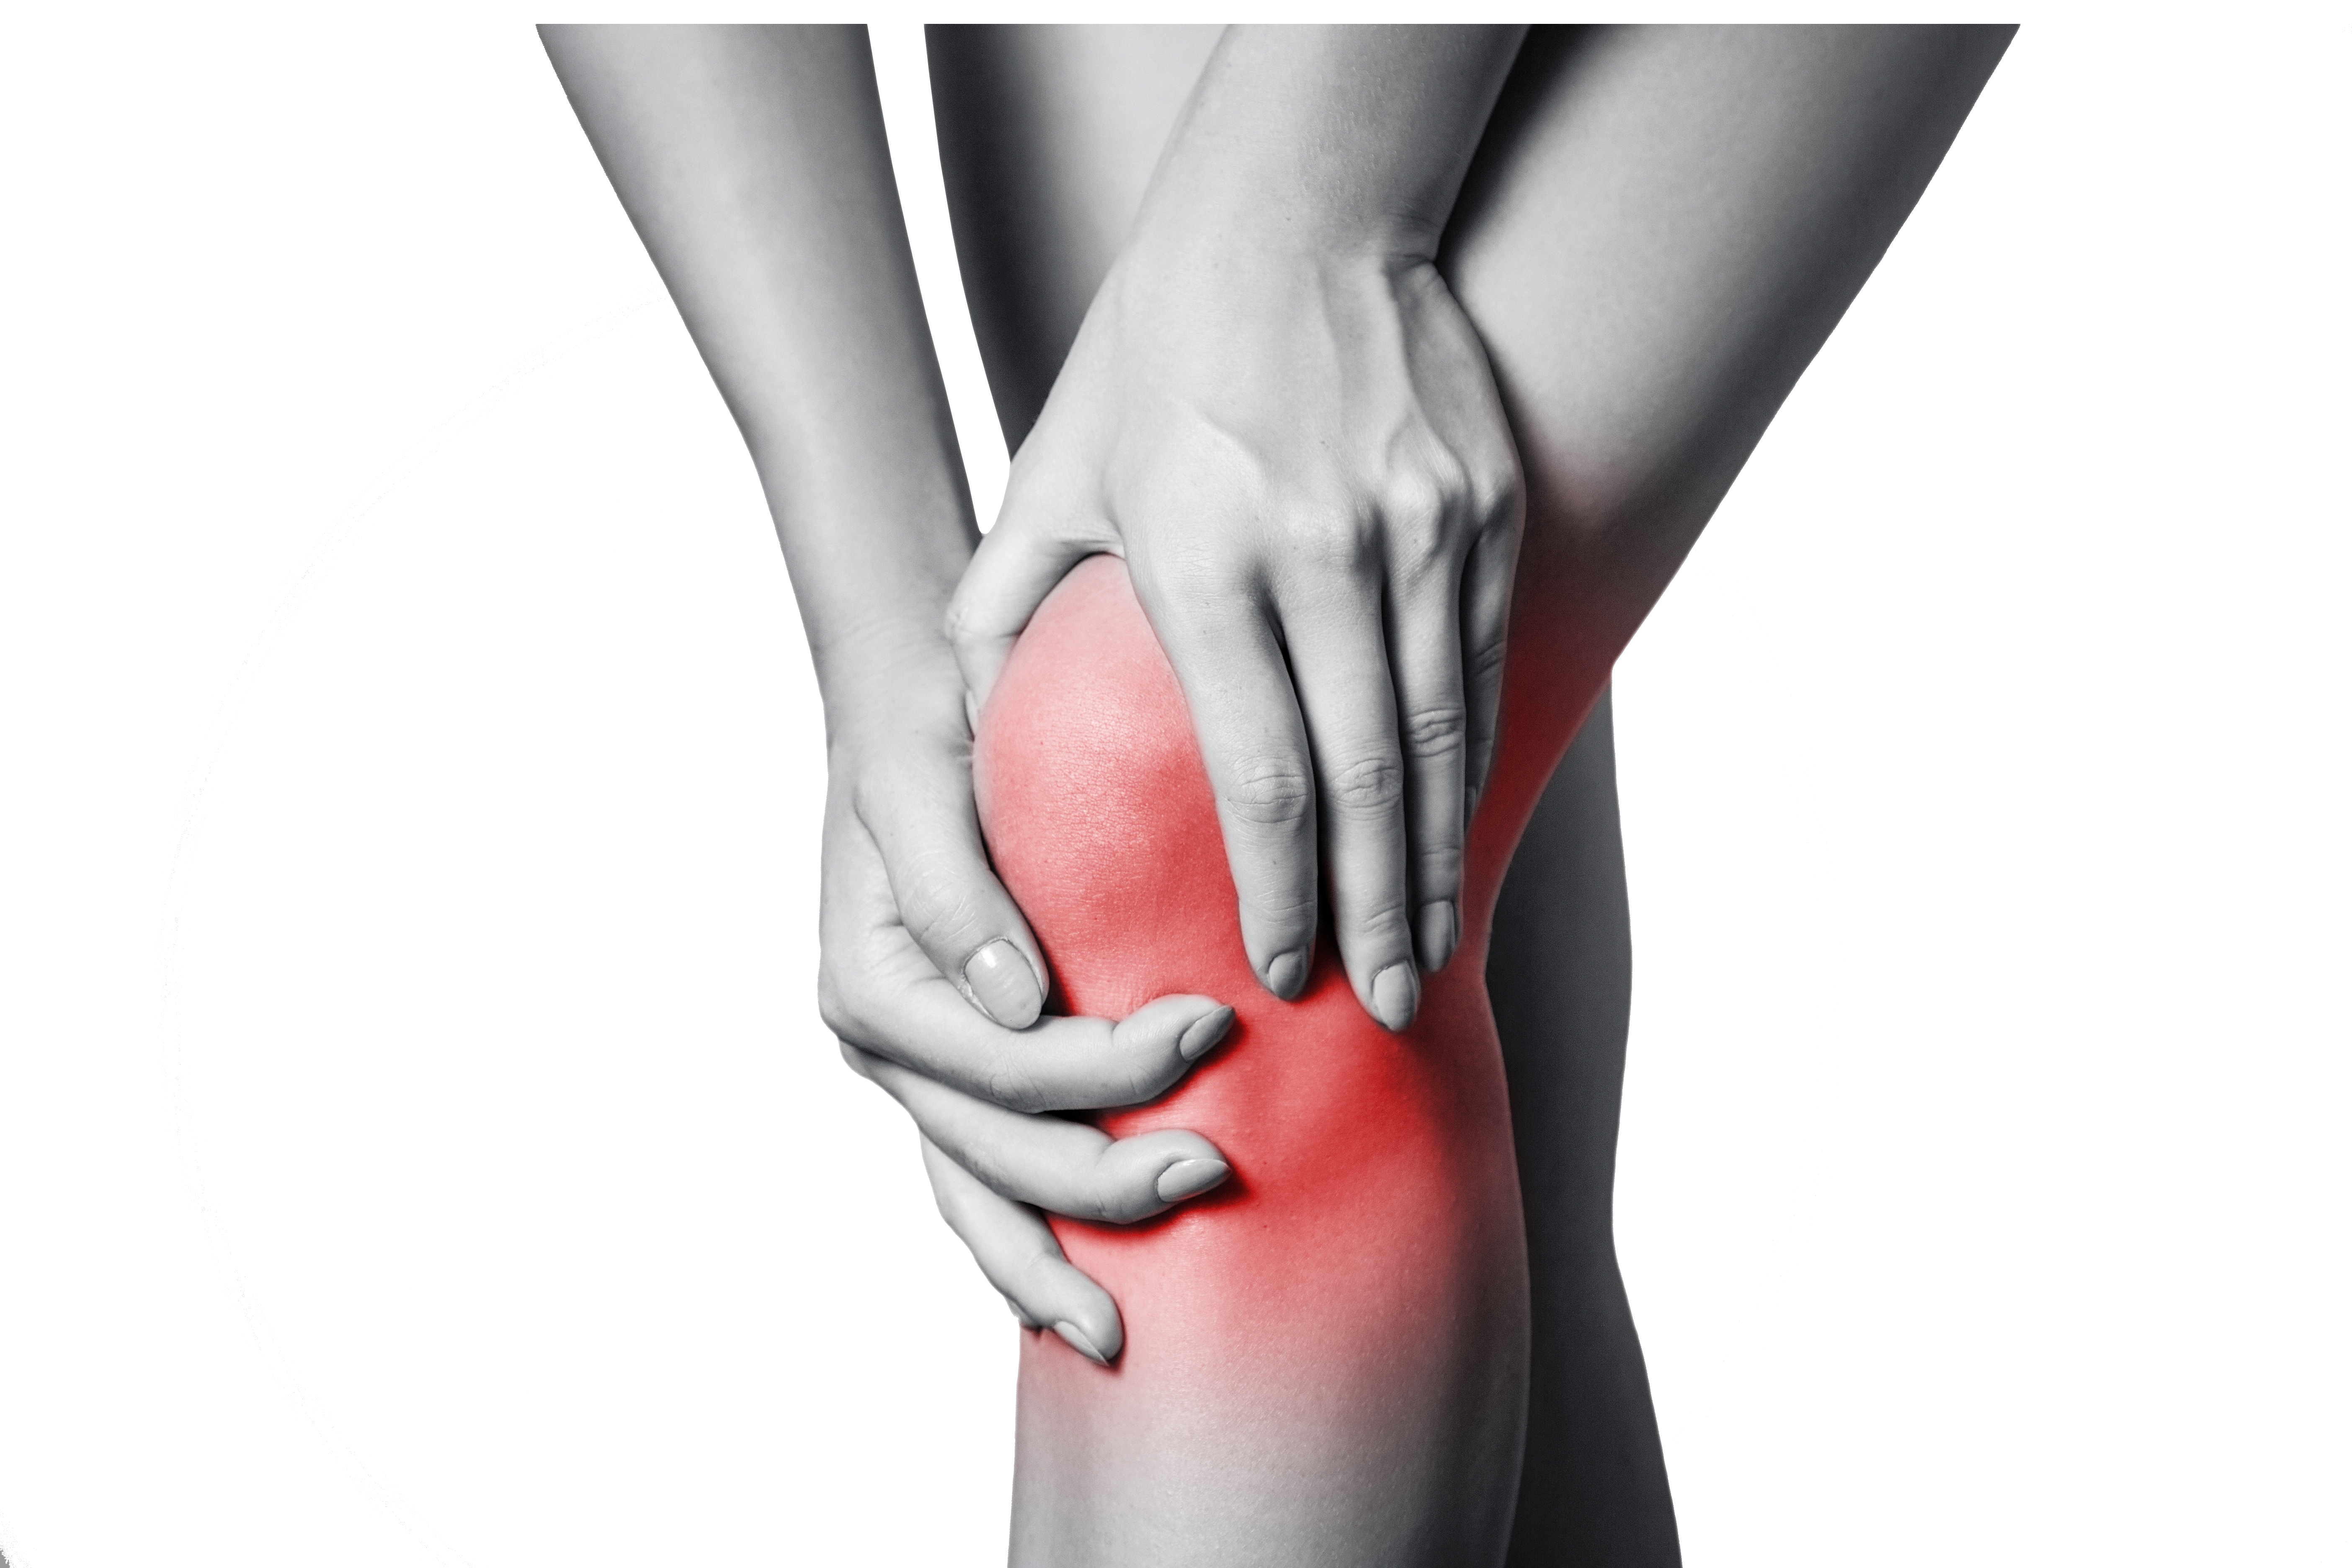

Infračervené lampy jsou pokročilé zdravotnické přístroje, které využívají infračervené záření k úlevě od bolesti a podpoře regenerace tkání. Ideální pro muže i ženy, tyto lampy nabízejí účinné a neinvazivní řešení pro různé zdravotní problémy. Značky jako BEURER a SAFE LASER poskytují špičkové modely s pokročilými funkcemi pro maximální pohodlí a efektivitu při domácím použití. Infračervené lampy podporují prokrvení a urychlují hojení, čímž mohou být skvělým doplňkem kloubní výživy.

Používání infračervených lamp přináší řadu výhod. Infračervené záření proniká hluboko do tkání, kde podporuje prokrvení a urychluje proces hojení. Tento typ terapie je vhodný pro léčbu bolesti svalů, kloubů a dalších zdravotních problémů. Produkty od BEURER a SAFE LASER jsou vybaveny pokročilými funkcemi, které zajišťují bezpečnost a snadné použití. Infračervené lampy mohou být také skvělým doplňkem kloubní výživy, protože podporují regeneraci a celkovou pohodu.

Pro dosažení nejlepších výsledků je důležité správně používat infračervené lampy. Před použitím se ujistěte, že oblast, kterou chcete ošetřit, je čistá a suchá. Umístěte lampu ve vzdálenosti doporučené výrobcem a nechte působit po dobu 10-15 minut. Tuto proceduru lze opakovat několikrát denně podle potřeby. BEURER a SAFE LASER nabízejí modely, které jsou snadno ovladatelné a bezpečné pro domácí použití. Infračervené lampy jsou vhodné pro muže i ženy všech věkových kategorií a mohou být účinně využívány jako součást každodenní péče o zdraví.